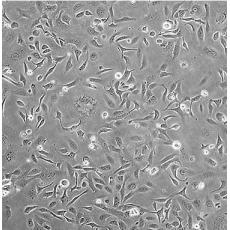

SK-OV-3 [SKOV3]

中文名稱 人卵巢癌細胞

組織來源 卵巢漿液性囊腺癌;腹水轉移;女性

生長特性 adherent

形態特征 epithelial

細胞描述 SK-OV-3 cells are resistant to tumor necrosis factor and to several cytotoxic drugs including diphtheria toxin, cis-platinum and adriamycin.